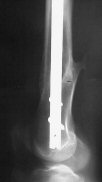

I presented a series of ~25 such cases at EuroTrauma'2004. Many cases were discussed here. I attach am example. Look also recent cases at http://www.hwbf.org/hwb/conf/alex58/scfx.htm,

http://www.hwbf.org/hwb/conf/alex63/alex63.htm

At that moment we had in stock only the 10 mm solid nails so of course there was no idea about early weight bearing. But it was quite enough for early knee ROM excersises (see attached). Two locking screws through the distal block provided that.